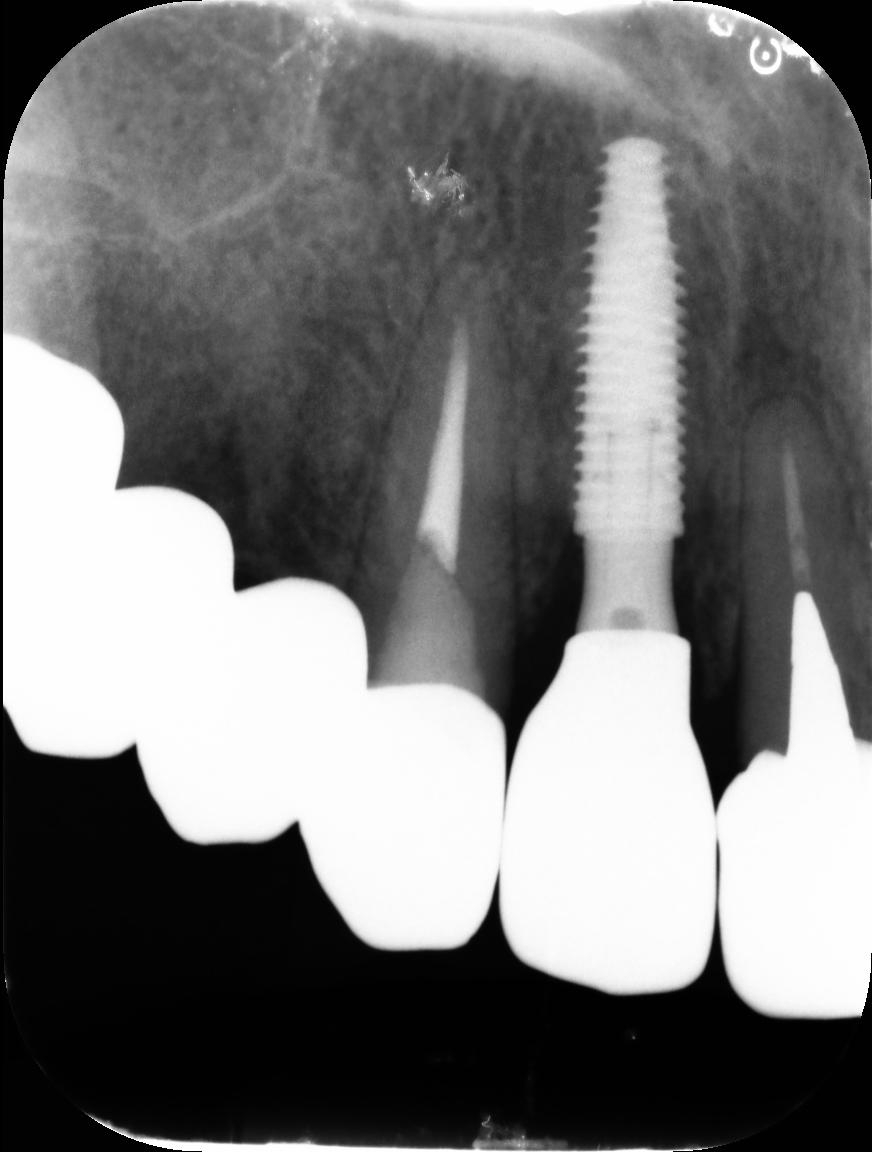

4.右上5が折れたために、インプラント抜歯即時埋入をおこなったインプラント治療のケース。

Before

枚方市のインプラントの症例

T・T 様 女性 40代

症状としては、 右上5番の歯が折れてしまった。保存することは不可能な状態であった

治療法としては、患者様は、歯が折れたことを主訴に来院。インプラント治療を希望したため、抜歯した当日に、インプラント埋入をおこなって、骨欠損部には人工骨を補填した。1か月半後にインプラントが骨と結合していることを確認できたため、光学印象を行い、2か月後に、最終補綴物として、アバットメントとジルコニアクラウンの装着を行いました。

治療結果としては、抜歯したと同時にインプラントを埋入することで、抜歯した穴が自然に治る過程で、インプラントの骨結合と組織の治癒が同時に行われるために、2か月という治療期間で治療を終了することができたことと、機能面・審美面でも回復を行うができた。

治療の期間・回数:約2か月、インプラント抜歯即時埋入から最終補綴物装着まで4回

治療の価格:352,000円(税込)

治療費の内訳:インプラント基本料(フィックスチャー及び手術費用、投薬費用、レントゲン費用、インプラント上部費用(アバットメントおよびジルコニアクラウンの費用用)330000円(税込み)。オプション、抜歯即時埋入加算(人工骨費用を含む) 22000円(税込み)

治療のリスクや副作用:手術後に、痛みや腫れ、出血、合併症などを引き起こす可能性があります。噛む感覚がご自身の歯と異なる場合があります。見た目がご自身の歯と異なる場合があります。手術後にメインテナンスを継続しないと、インプラントが抜け落ちる可能性があります。